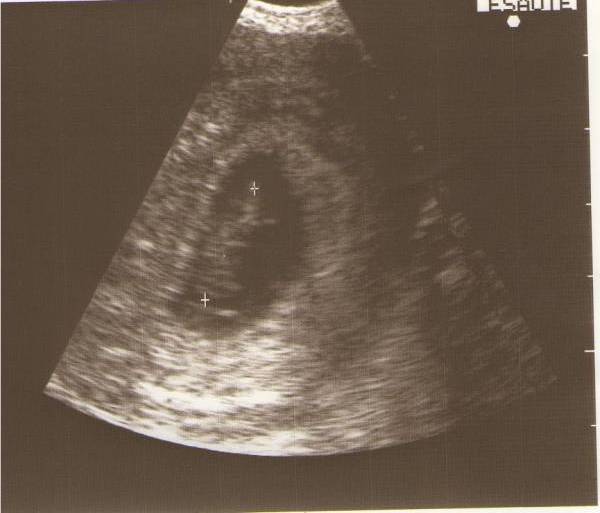

Tegnapi két kép:

Kép

Adatok pedig:

a petezsák 47mm

a baba 19mm

Óriás bébi :lol: